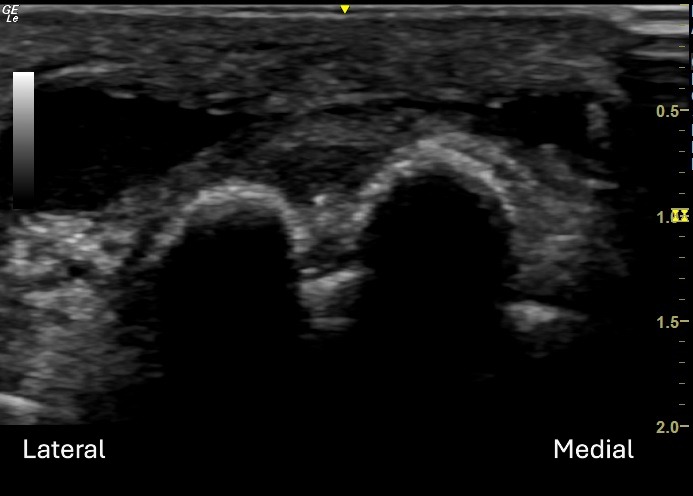

Unlabeled Short Axis view of the medial plantar forefoot.